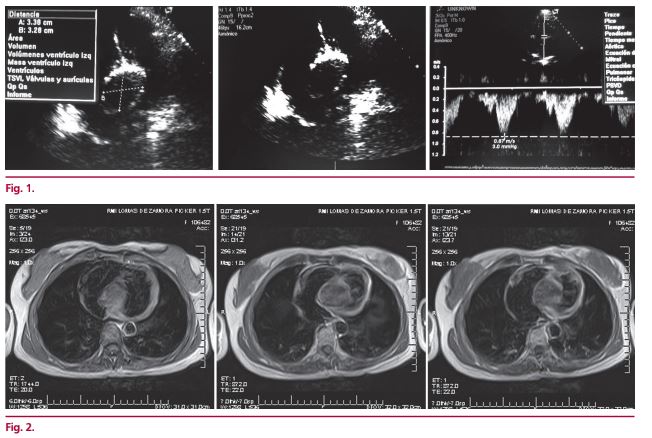

Tumor cardíaco

IMÁGENES EN CARDIOLOGÍA